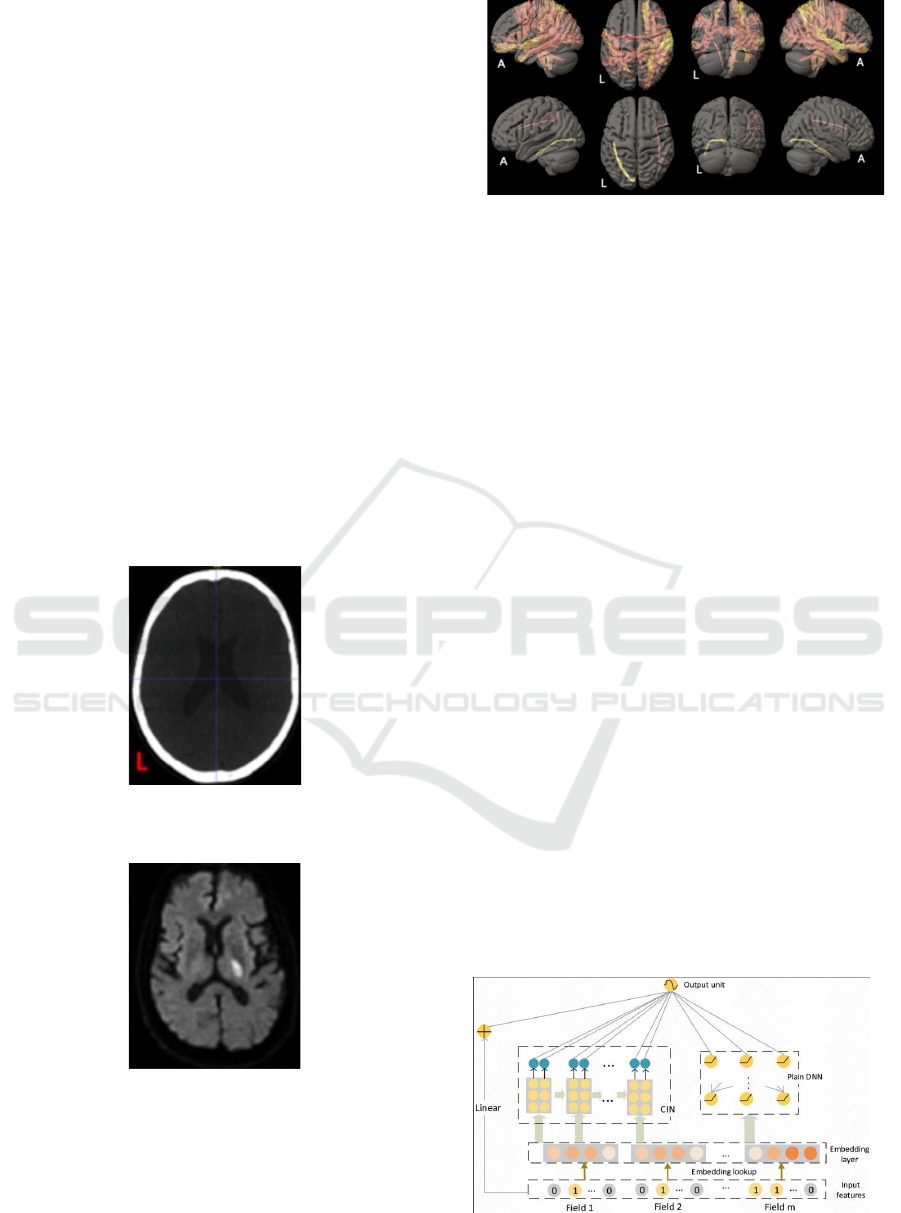

Consequently, the initial NCCT image and

preprocessed imaging result are presented as Figure 1

and Figure 2, and then a reconstructive 3D image has

already been created to show all global physical

features in Figure 3.

Figure 1: Original image of NCCT (Picture credit:

Original).

Figure 2: Preprocessed image of NCCT (Picture credit:

Figure 3: 3D reconstructive cephalic imaging (Picture

credit: Original).